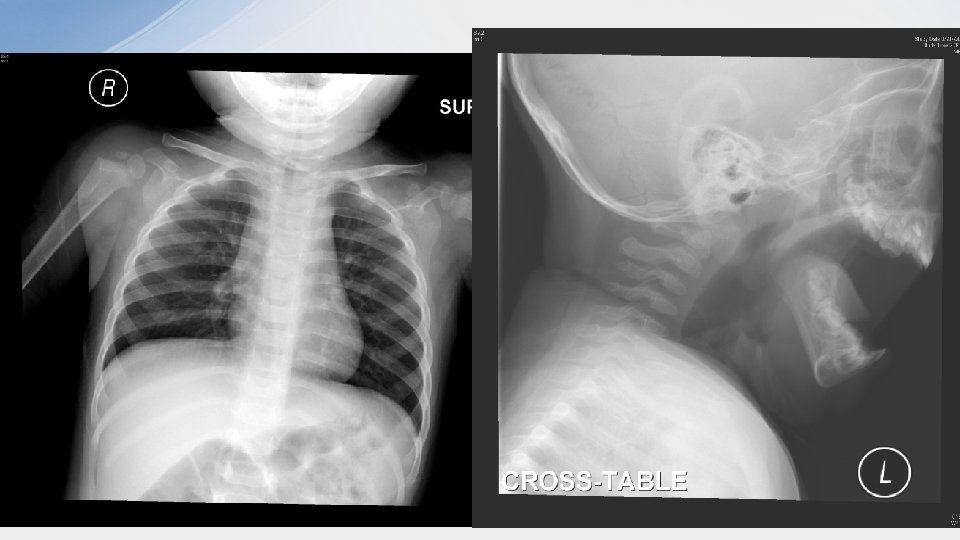

Case 1 • • 14 m / F FTNSD Fever, cough, noisy breathing and SOB on DOA TOCC negative Pulse 140 bpm Sp. O 2 97% (RA) Temp 38. 3 X rays were performed

• 1. What are the x ray findings? –steeple sign –supraglottic distension

• 2. What is the diagnosis? – Croup • 3. How would you assess the severity? – – – by the presence or absence of stridor at rest the degree of chest wall retractions air entry pallor or cyanosis mental status